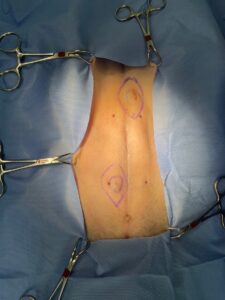

画像4:上記の術中写真